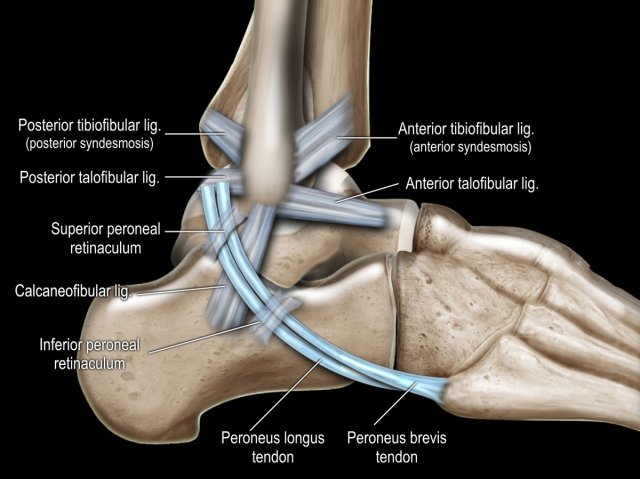

Ligaments

There are three ligaments on the lateral side:

1. anterior talofibular ligament (ATFL)

2. calcaneofibular ligament (CFL)

3. posterior talofibular ligament (PTFL).

The ATFL runs from the lateral malleolus anteriorly to the lateral border of the talus.

It has a transverse orientation and is best seen on axial images.